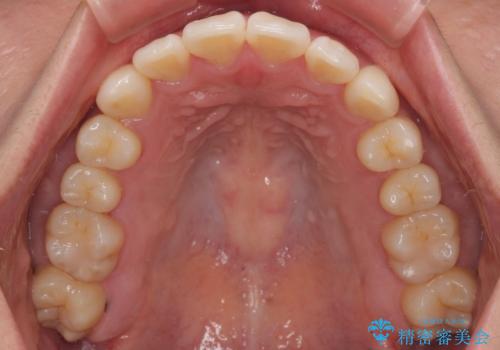

初診時、上下顎ともに歯列の不正が認められ、特に左下の小臼歯が大きく歯列から外れている状態でした。その影響により、下顎の正中が左側へシフトしており、見た目だけでなく噛み合わせにも影響が出ていました。

矯正中の見た目にも配慮し、プラスチックブラケット+コーティングワイヤーの目立ちにくい審美装置を採用しました。

「歯並びと正中が整って、自信をもって笑えるようになった」

と大変ご満足のお言葉をいただきました。